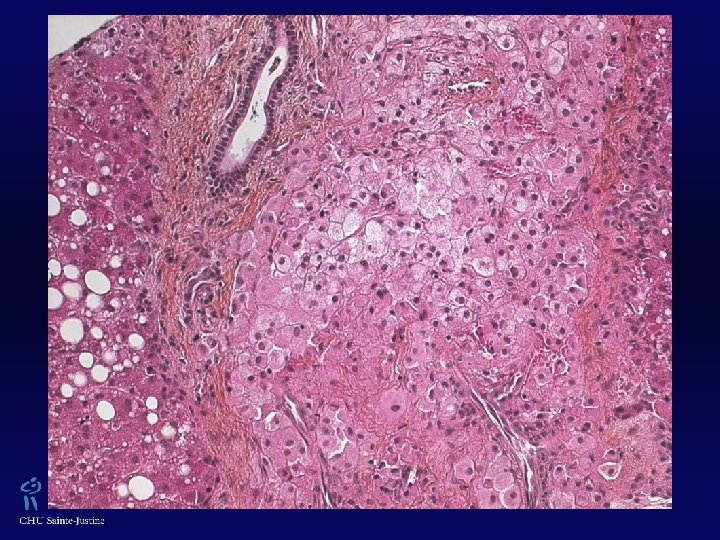

XGJ w Trois types cellulaires : w Cellules mononucléées w Cellules géantes mutinucléées, ± de type cellules de Touton (› lésions cutanées, absentes dans les formes jeunes) w Cellules fusiformes w ± Vacuoles cytoplasmiques, avec aspect xanthomateux w Éosinophiles 0/+++ w Vimentine +, CD 68 +, Facteur XIIa +, Fascine + w Protéine S 100 ± w CD 1 A -, absence de granules de Birbeck (ME)

Histiocyte Lysosomes contenant des inclusions denses

Hépatocyte Mitochondries normales Gouttelettes lipidiques Inclusions dans RE d’α-1 -antitrypsine